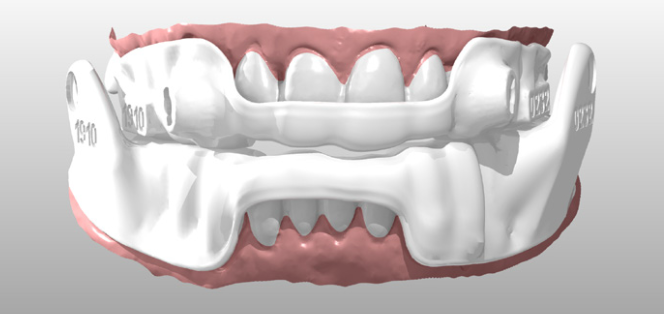

The full arch scans were exported to ResMed, where the 3D model was aligned with a virtual articulator and the Narval CC appliance designed using a completely digital workflow — no physical models, no alginate, no stone.

On fitting day, the device was checked for retention, occlusion, TMJ comfort, connector mechanics, and protrusion accuracy. The fit was accurate and comfortable — reinforcing the benefits of a fully digital impression and design workflow over traditional methods.

View CS 8200 →Intraoral Scanner

Digital impression capture with CS 3600 acquisition software. Multiple bite registrations, undercut analysis, and accurate protrusion recording for MAD design.